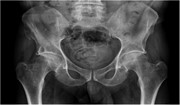

Recurrent gluteal haematoma: two internal iliac artery-associated bleeding points

Bilal Rafique and others

Journal of Surgical Case Reports, Volume 2016, Issue 6, June 2016, rjw107, https://doi.org/10.1093/jscr/rjw107